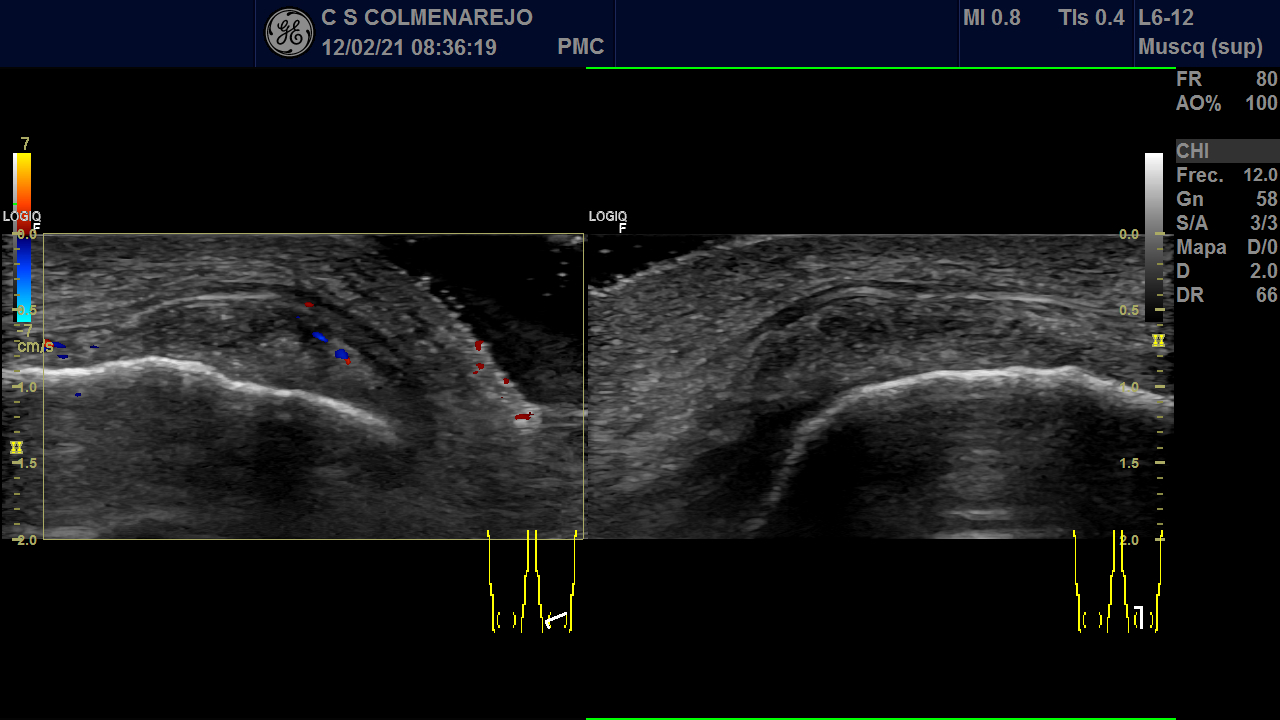

Eco rodilla izq: 02/21: Sinovitis prerotuliana y suprarotuliana, derrame infrarotuliano. Tendón del cuádriceps de estructura fibrilar. Signos de pequeño derrame y sinovitis en bursa prerrotuliana y en recesos laterales. Bursitis prerrotuliana con sinovitis Doppler +. Ligamento colateral medial sin hallazgos. No quiste de Baker. Cartílago de ecogenicidad normal disminuido el grosor y calcificaciones en zona medial.